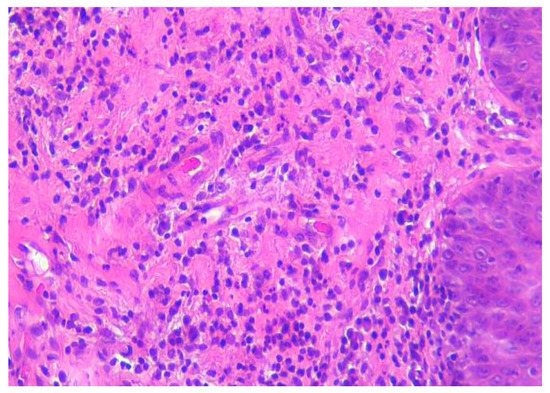

2. Case Presentation

3.2. Oral Eosinophilic Granuloma